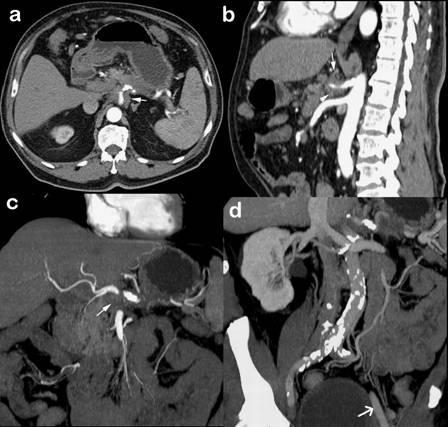

A 71-year-old man with pancreatic body cancer after neoadjuvant gemcitabine-based chemotherapy was referred for surgical treatment. Abdominal CT scan was performed and showed a locally advanced tumour (Fig. 1). Complete tumour screening including chest CT and positron emission tomography (PET-CT) was performed and discarded extrapancreatic disease. Laboratory tests were all within normal range, except for increased CA 19-9 level.

Detailed analysis of a sequence of abdominal CT scans performed before the surgical procedure revealed a marked decrease in tumour size after chemotherapy, but the celiac axis remained involved (Fig. 1).

During surgical exploration, the tumour was confined to the pancreas and nearby structures, and there were no signs of liver metastasis or peritoneal dissemination. Intraoperative palpation of Aorta confirmed the presence of diffuse calcification but left external iliac artery was not compromised (Fig. 1d)

FIGURE 1. Preoperative CT scan.

a. Axial view shows a large tumour in the body of the pancreas involving celiac axis (arrow).

b. Sagittal view shows involvement of celiac trunk (arrows). Mesenteric trunk is free.

c. Coronal view shows tumour in the body of the pancreas with invasion of celiac axis (arrow).

d. 3D reconstruction shows Aorta diffusely calcified. Left external iliac artery (arrow) is spared.